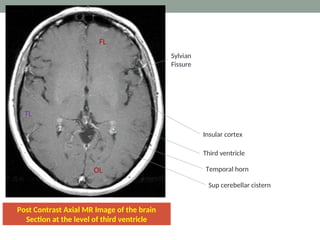

Post Contrast Axial MR Image of the brain

Section at the level of third ventricle

TL

FL

OL

Sylvian

Fissure

Temporal horn

Sup cerebellar cistern

Insular cortex

Third ventricle